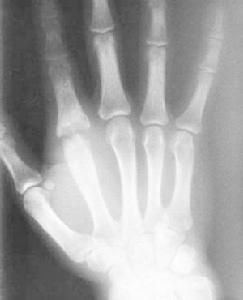

關節周圍軟組織腫脹影,骨質疏鬆,以後關節間隙變窄,骨盾破壞,反應發現有質增生。晚期關節呈纖維性或骨性融合,死骨形成,關節脫位或間脫位。X線檢查時,在早期由於關節液增加而關節囊腫脹,間隙增寬,骨端逐漸有脫鈣現象。如關節面軟骨有破壞,則關節間隙變窄。有時可講發骨骺滑脫或病理性脫位。較晚期,關節面下骨質呈反應性增生,骨質硬化,密度增加。最後關節軟骨完全溶解,關節間隙消失,呈骨性或纖維性強直,或餅發病理性脫位。其X線表現為:

1. 早期關節內有化膿性炎症時,關節周圍軟組織常有充血及水腫,表現為軟組織厚於健側,層次不清。關節囊因關節內積液而膨脹,脂肪層被推移呈弧形。偶爾可見關節間隙輕微增寬,應與健側對照,才不會漏診。

2.關節間隙狹窄化膿性細菌進入關節後首先引起的滑膜炎。滲出液內含有大量中性白細胞。白細胞死亡後所釋放出的大量溶蛋白酶、很快地溶解關節軟骨。根據關節軟骨被破壞的程度,常於發病後短期內出現關節間隙狹窄,甚至完全消失。

3.關節面改變關節軟骨被破壞後,即可進一步破壞軟骨下骨質。最早出現在關節面的相互接觸部分,即負重部分。表現為關節面模糊和不規則。繼而形成較大的破壞區,形成死骨。由於機體的修復作用,破壞區周圍因骨質增生而密度增大,關節邊緣有唇樣骨質增生。當骨小梁貫穿關節間隙以聯接兩側骨關節面時稱之骨性強直。

4.關節軟骨及骨質破壞嚴重時可引起脫位或半脫位一般青少年和成人,常因關節軟骨破壞形成骨性強宜,而兒童多發生骨端的破壞,吸收,引起病理性脫位。